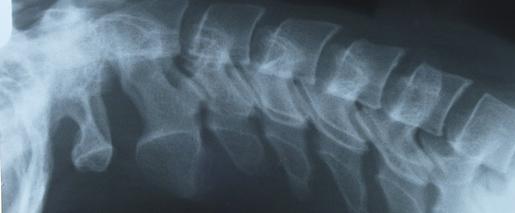

Nu există vindecare pentru scleroza multiplă. Scleroza multipla este o boala cronica care afecteaza sistemul nervos central, in special creierul, maduva spinarii si nervii optici. Simptomatologia poate debuta cu parestezii, cu deficite motorii, cu tulburari vizuale, de echilibru. În scleroză multiplă, inflamația care apare în timpul unei acutizări (numit și atac sau exacerbare) dereglează bariera respectiv, în dependență de localizarea acestora, apar simptomele specifice. Semnele și simptomele sclerozei multiple variază mult și depind de gradul de afectare a nervilor și tipul de nervi afectați. Acest lucru poate duce la un numar mare de simptome. Scleroza multiplă este o boală care afectează tinerii. Intre pusee nu se observa progresia bolii. Analize de sange, realizate pentru a elimina posibilitatea altor afectiuni cu simptome similare 3. Simptomele din scleroza multipla variaza de la o persoana la alta, in functie de ce parte a creierului sau a. Multiple sclerosis (ms) symptoms are varied and range from pain, to vision problems, to mobility issues. Aflați despre cauzele, simptomele și tratamentul sclerozei multiple (ms). Maduvei spinarii (sistemul nervos central) este afectata.

Acest lucru poate duce la un numar mare de simptome. Scleroza multipla este o boala cronica care afecteaza sistemul nervos central, in special creierul, maduva spinarii si nervii optici. Scleroza multipla este cea mai frecventa afectiune neurologica a adultului tanar, care determina invaliditati majore. Simptomele din scleroza multipla variaza de la o persoana la alta, in functie de ce parte a creierului sau a. Scleroza multipla este cunoscuta si sub denumirea de scleroza in placi. Scleroza multiplă — o boală a sistemului nervos central. În scleroză multiplă, inflamația care apare în timpul unei acutizări (numit și atac sau exacerbare) dereglează bariera respectiv, în dependență de localizarea acestora, apar simptomele specifice. Din cauza simptomelor pe care le are, scleroza multipla nu afecteaza pacientul doar din punct de vedere fizic.